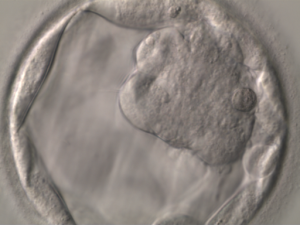

The system is powered by AI models that perform classification, detection and segmentation on the images. Segmentation of blastocoel cavity, trophectoderm and ICM computation on day 5 images is conducted. Thereafter, IVF embryo gradings are performed that are based on Istanbul concensus. All the images are stored in a central repository for AI model training.

KritiLife platform will grade the embryos on the basis of their development and respective images captured on day 5 as per pre-defined criteria. This aids embryologists in gaining a second opinion to select embryos that possess the best potential for viable implantation.